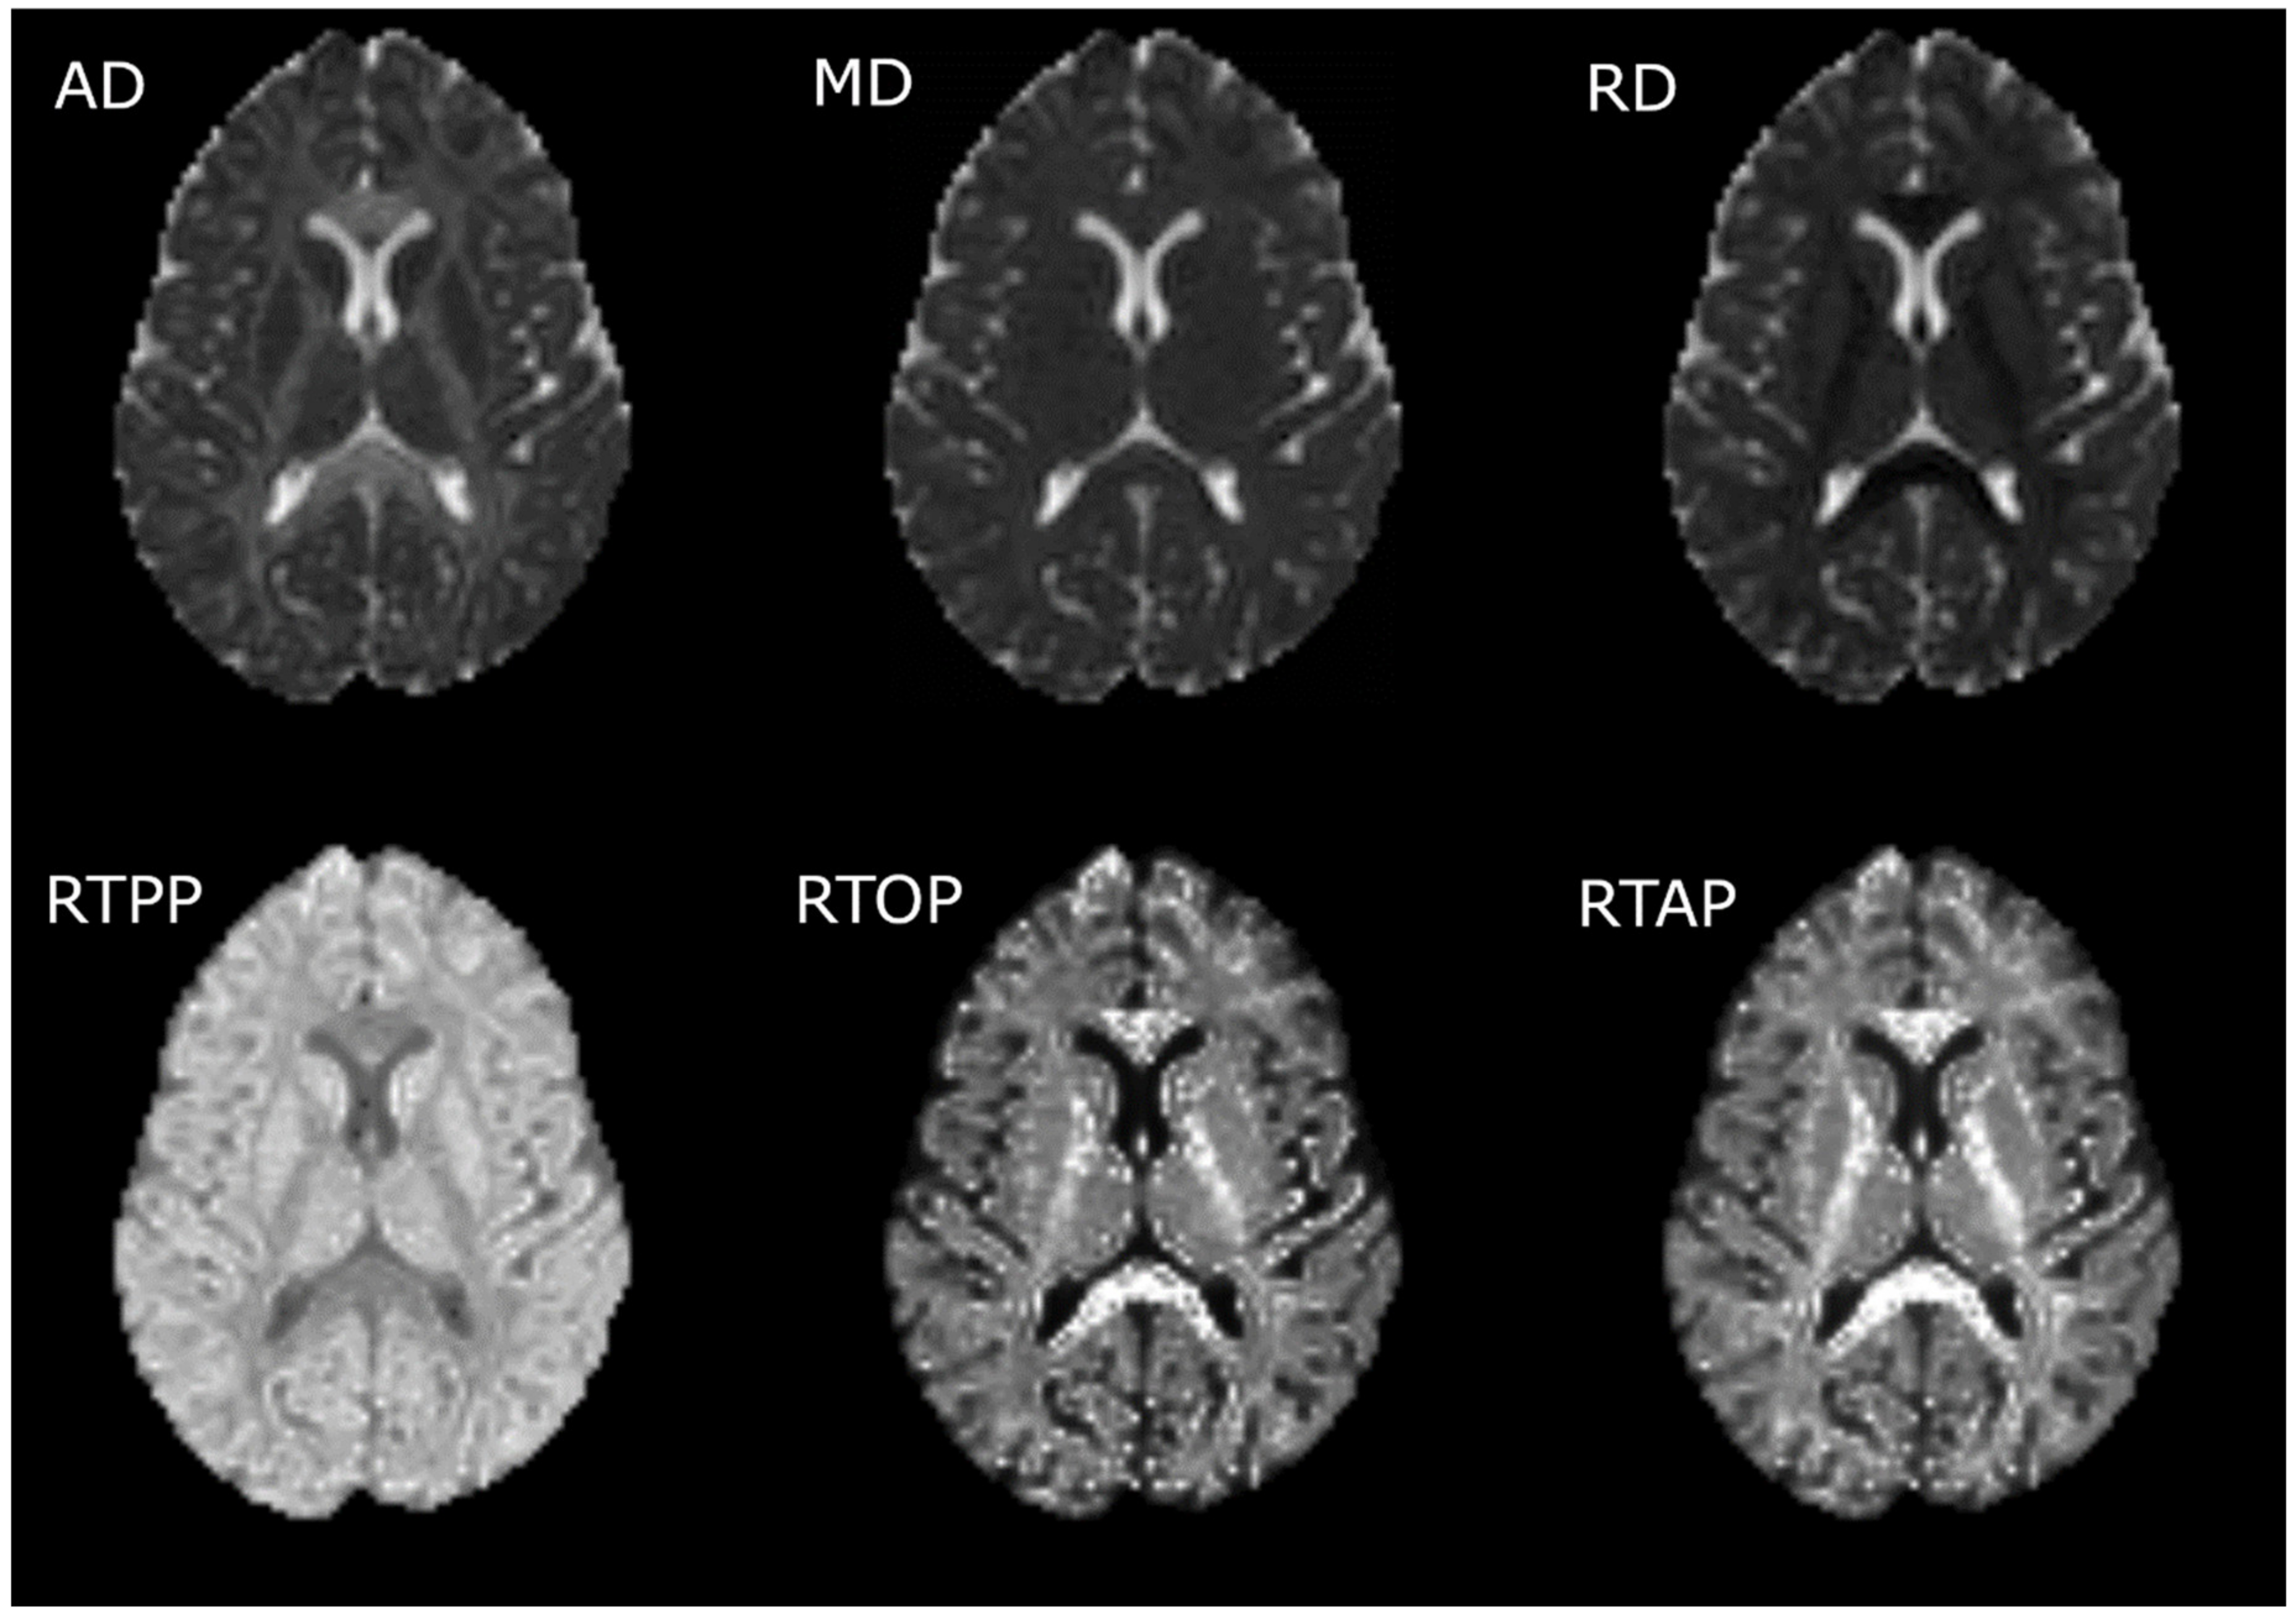

2.3.2. Calculation of the Diffusion Measures